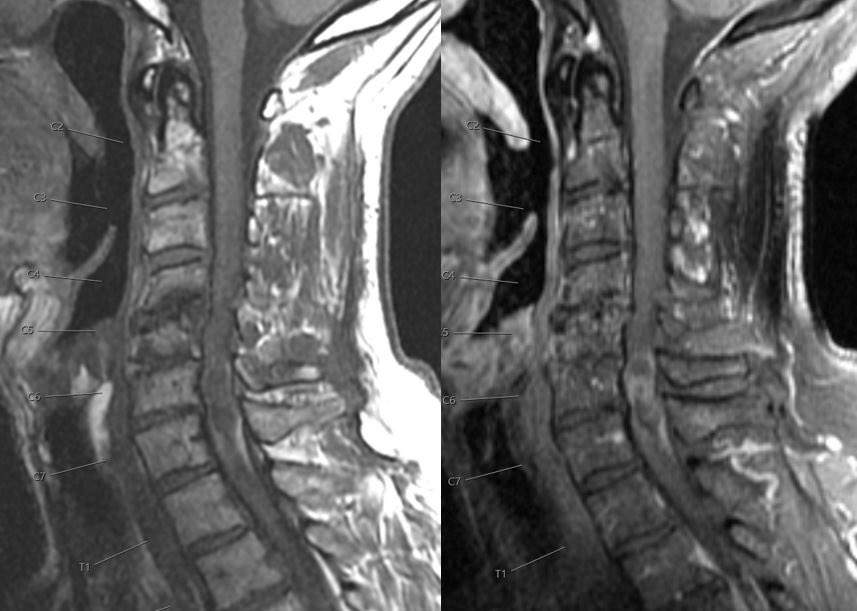

What is the most likely diagnosis in this 65 y/o M presenting w/ leg weakness, hyperreflexia, spasticity and absent vibration sense in the LE? #neu